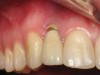

Figure 2  Clinical photograph of an implant restoration replacing the congenitally missing maxillary left lateral incisor. Note the cyanotic color changes, due to inflammation and cement, of the marginal gingiva in a 31-year-old female patient with thin biotype.

Figure 2